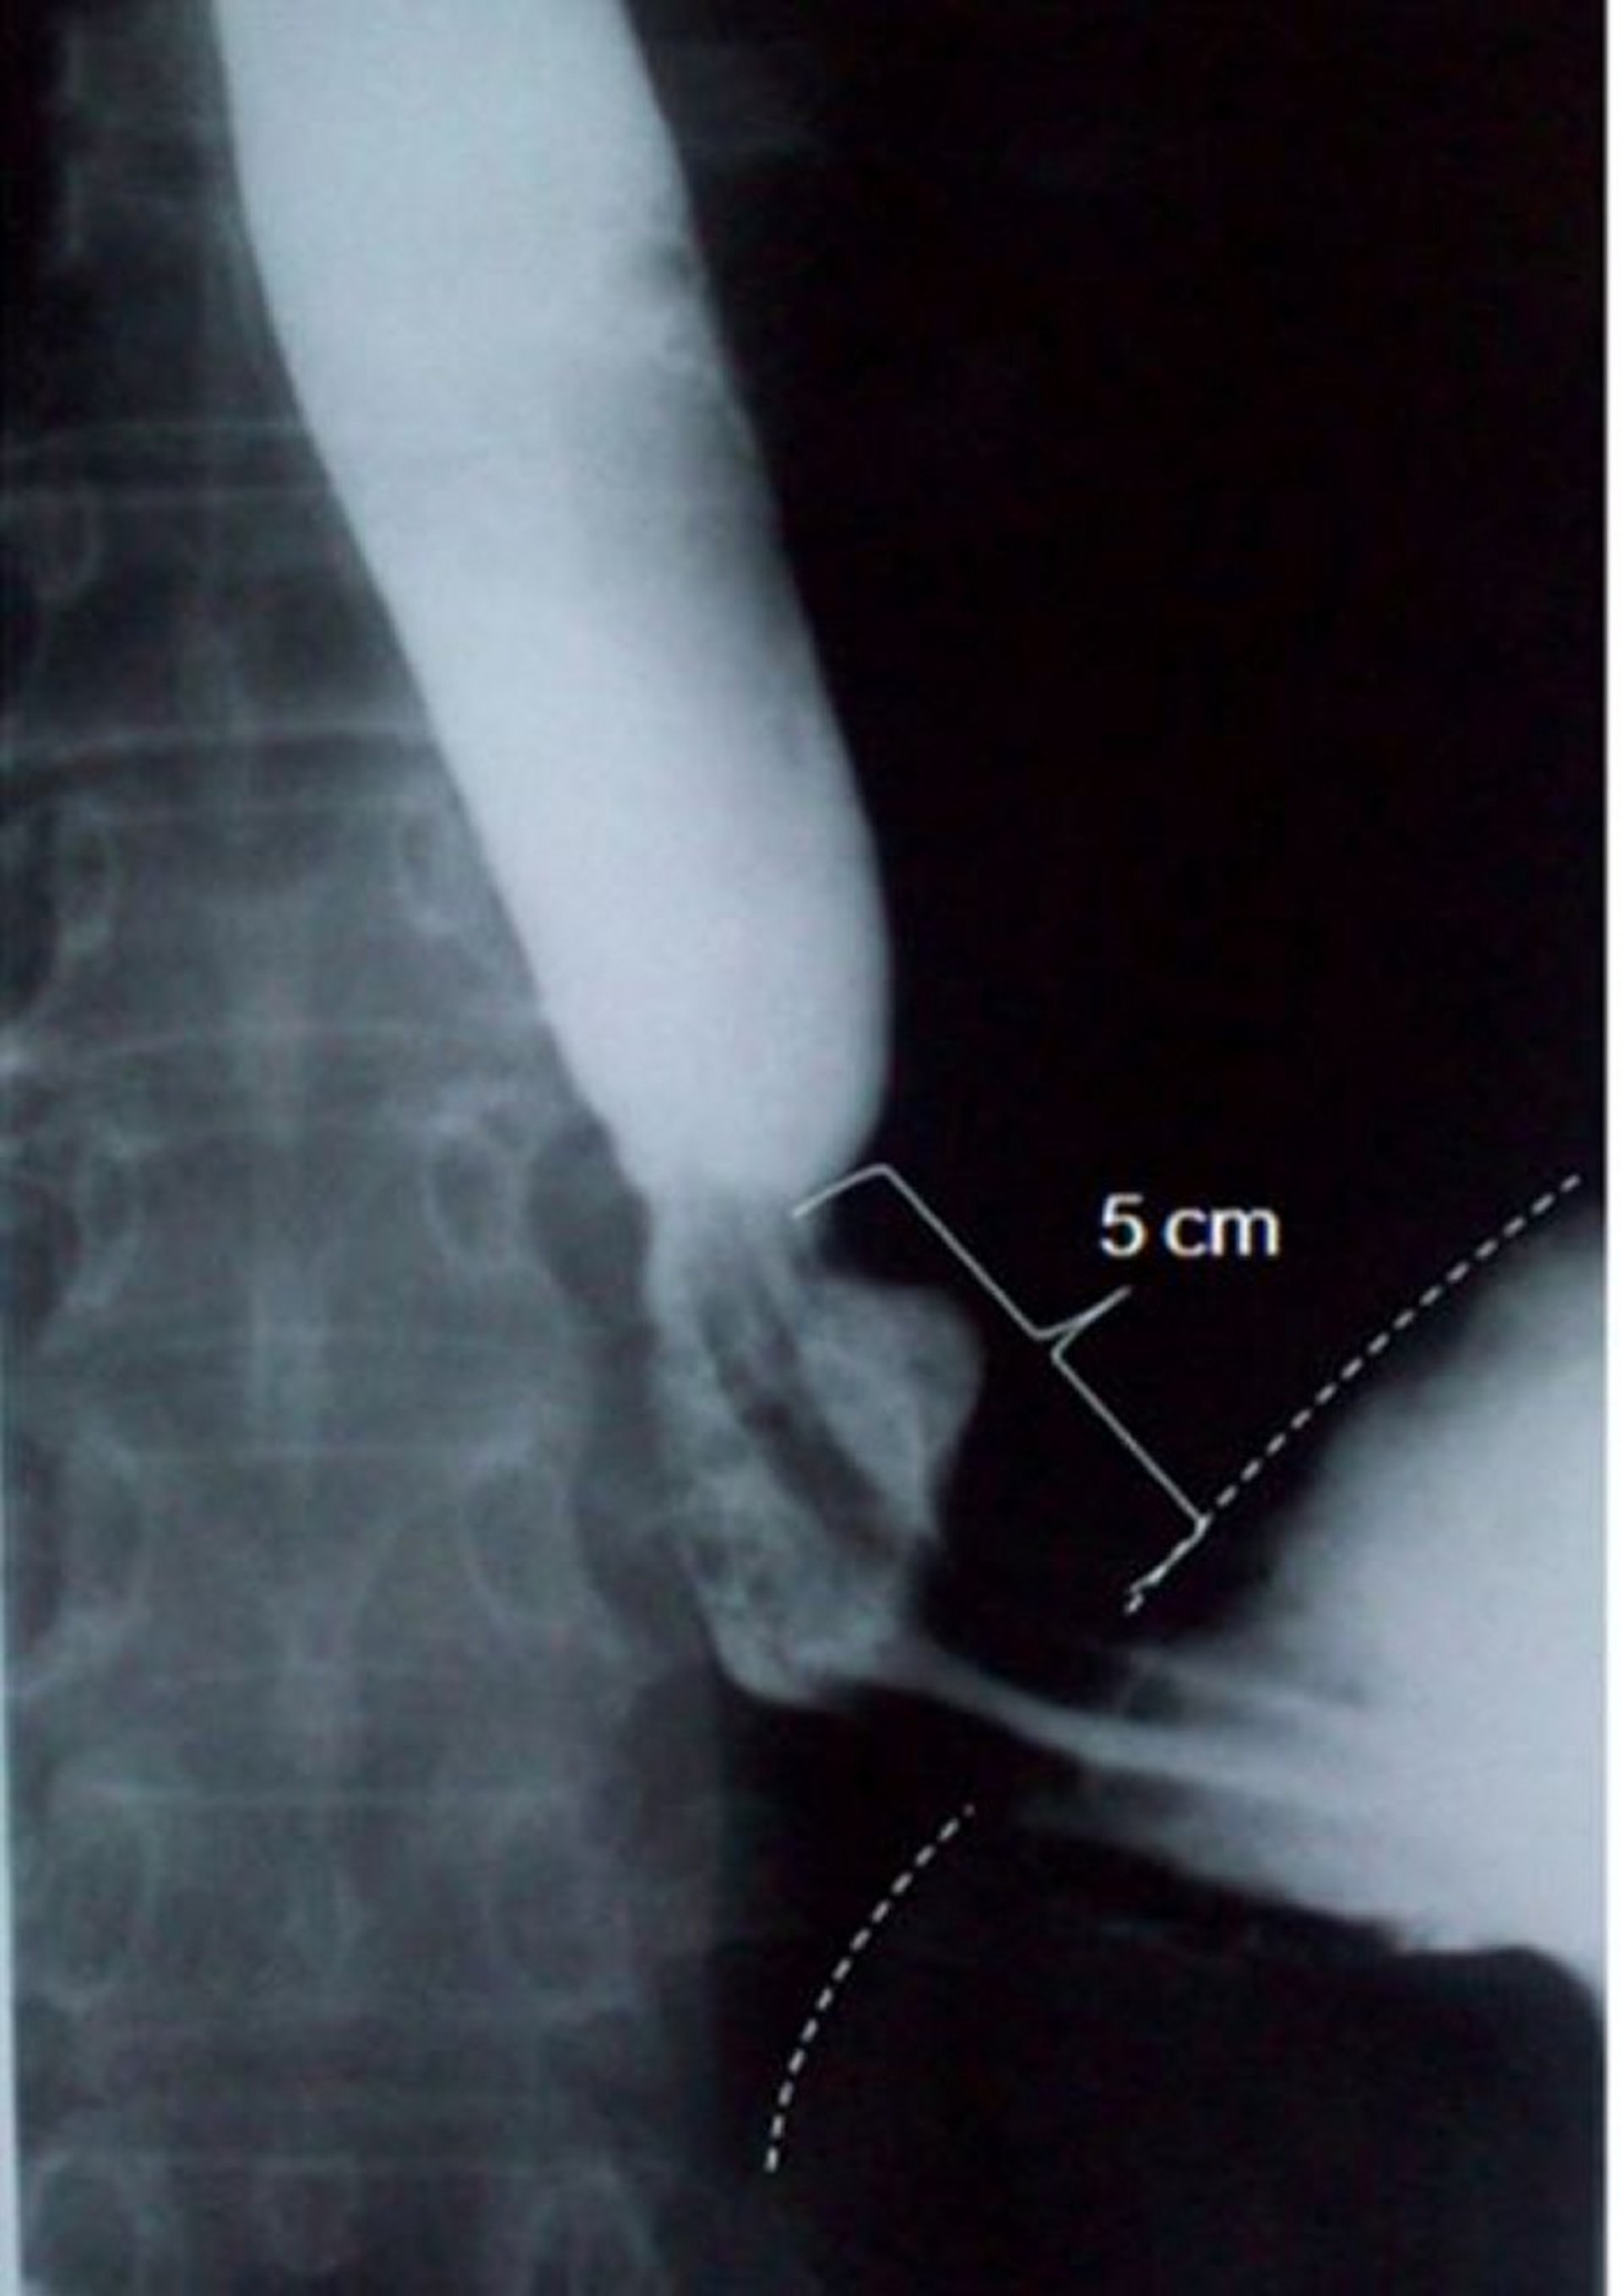

Barium Swallow Showing Sliding Hiatus Hernia

This image shows a sliding hiatus hernia measuring 5 centimeters (5 cm) in axial length (dashed line indicates the diaphragmatic border).